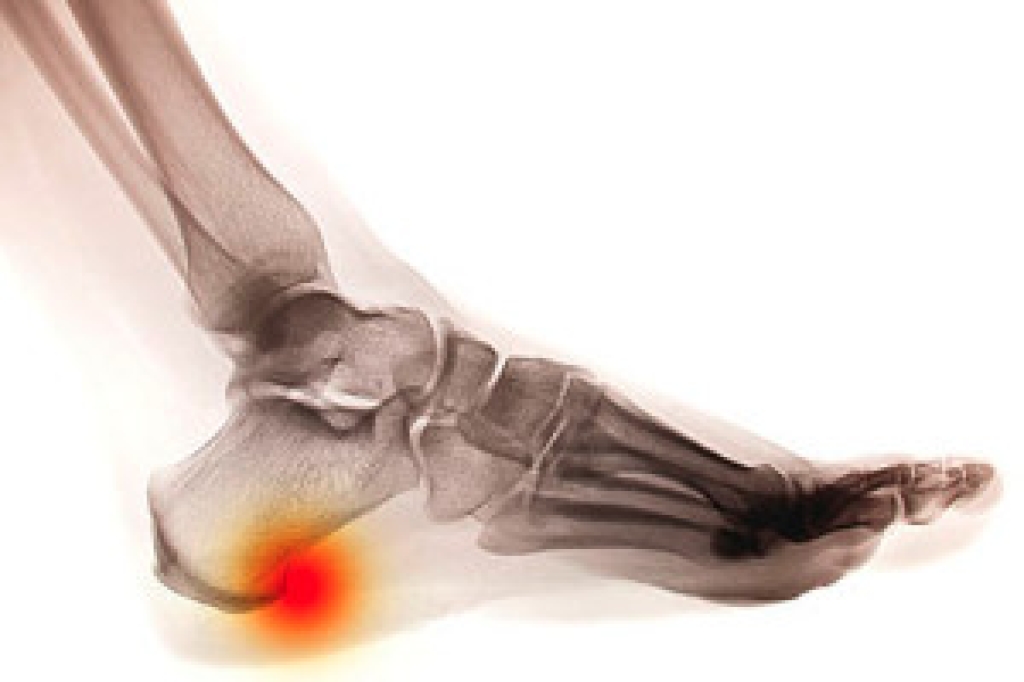

It is an unnatural feeling to fall, and it is considered to be a common occurrence among the elderly population. It can produce fear in accomplishing daily activities, and many people can experience serious injuries. Falling may occur from existing medical conditions that can impact balance. These can include vertigo, Parkinson’s Disease, or strokes. Environmental factors may play a significant role in contributing to the number of falls that people endure, consisting of cluttered living areas and poor lighting. It is helpful to have routine medical examinations performed, which can ensure medications are correct and current, and vision and hearing are normal. Many patients choose to have grab bars installed in their shower and toilet areas, as these can provide extra stability. If you would like more information about how falling can impact the feet, in addition to learning about effective fall prevention methods, please consult with a podiatrist.

Every 11 seconds, an elderly American is being treated in an emergency room for a fall related injury. Falls are the leading cause of head and hip injuries for those 65 and older. Due to decreases in strength, balance, senses, and lack of awareness, elderly persons are very susceptible to falling. Thankfully, there are a number of things older persons can do to prevent falls.

Falling can be a traumatic and embarrassing experience for elderly persons; this can make them less willing to leave the house, and less willing to talk to someone about their fears of falling. Doing such things, however, will increase the likelihood of tripping or losing one’s balance. Knowing the causes of falling and how to prevent them is the best way to mitigate the risk of serious injury.